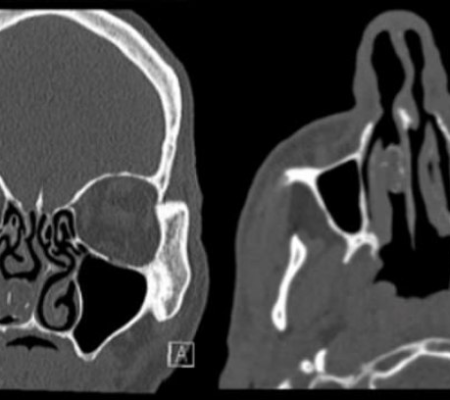

A ressonância, publicada pelo Jornal Britânico de Medicina, detectou uma massa de 1,9 por 1,1 centímetros. Quando os médicos fizeram o procedimento  cirúrgico que retirou a massa do local, eles perceberam que aquilo se tratava de um pequeno saco de maconha.

British Medical Case Reports / Divulgação